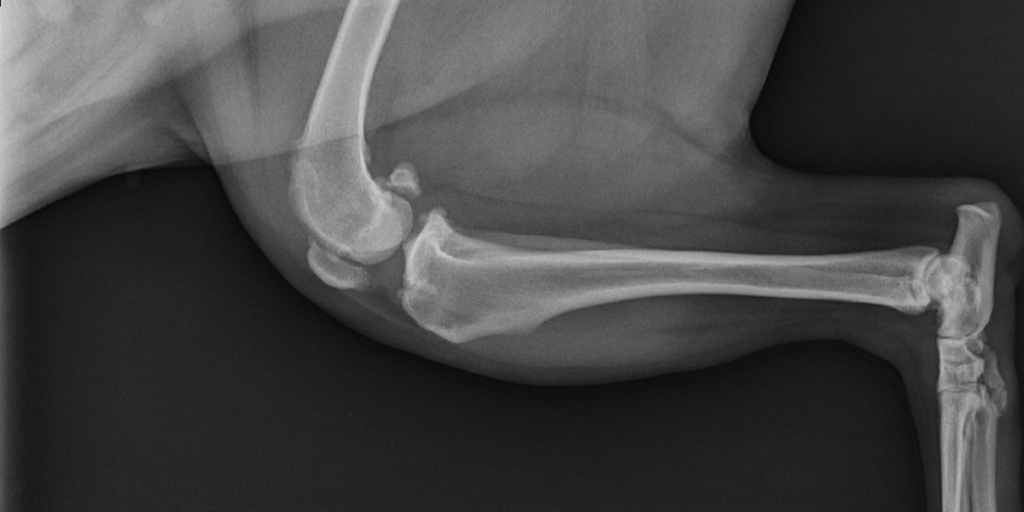

Ortopedija ili ortopedska kirurgija je grana kirurgije koja se bavi bolestima i liječenjem mišićno-koštanog sustava. Zbog kompleksnosti ozljeda pristup pacijentu je temeljit i sistematičan, a između ostalog uključuje opći pregled, promatranje kretanja, provjere opsega pokretljivosti i bolnosti, naposljetku se pristupa dodatnim dijagnostičkim pretragama kao što je rendgenološka pretraga. Najčešće ozljede uključuju prijelome kostiju i luksacije zglobova. Lom je svaki prekid kontinuiteta kosti, a luksacije su potpuna odvajanja krajeva kostiju koji se normalno spajaju u zglob. Glavni uzroci su prometne nezgode i padovi. Naša ambulanta koristi najmodernije implantate i tehnike sanacije dostupne u veterinarskoj medicini.